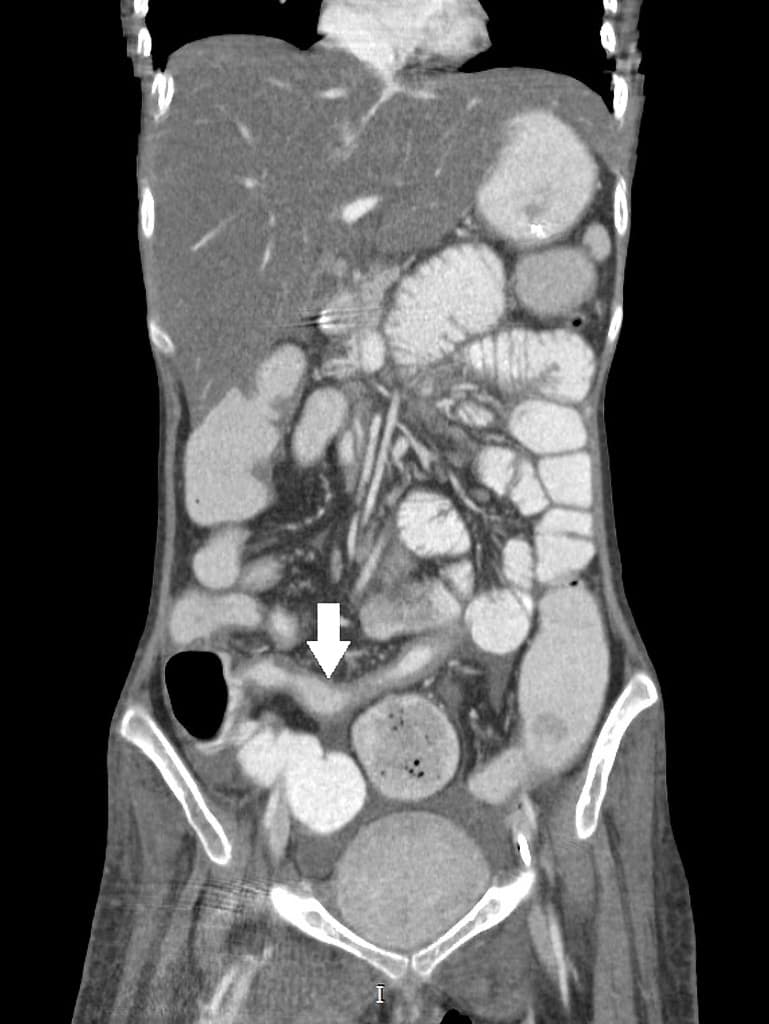

Biến dạng cấu trúc (architectural distortion) ruột kèm các đoạn hẹp (strictures) và các đường rò (fistulae) tại hố chậu phải, liên quan đến hồi cuối (terminal ileum). Cụ thể, phát hiện nhiều đường rò hồi – hồi (ileo-ileal) và hồi – đại tràng (ileocolonic), liên quan đến đại tràng lên và đại tràng xích-ma (sigmoid colon).

Có các đoạn hẹp (strictures) tại hồi tràng cuối và nhiều đường rò ruột – ruột (entero-enteric) và ruột – đại tràng (entero-colonic) tại hố chậu phải.

Có hiện tượng giãn đoạn trước hẹp (prestenotic dilatation) hồi tràng và đại tràng trực – xích-ma, mức độ thay đổi.

Hình ảnh học xác nhận bệnh Crohn thể biến chứng với các hình ảnh: biến dạng cấu trúc (distortion), giãn đoạn trước hẹp (prestenotic dilatation) tại hồi tràng giữa đến cuối, và nhiều đường rò ruột – ruột (entero-enteric), ruột – đại tràng (entero-colonic), kèm theo các đoạn hẹp (strictures).